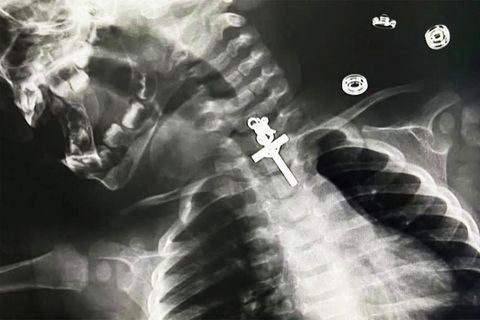

"Es ist ein Segen": Kleinkind verschluckt Kruzifix – OP glückt Gott sei Dank

"Es ist ein Segen" Kleinkind verschluckt Kruzifix – OP glückt Gott sei Dank

Sehen Sie im Video: Junges Mädchen verschluckt Kruzifix – OP glückt Gott sei Dank.

Diese Röntgenaufnahme ist von einem 10 Monate alten Mädchen, das in Peru ein Kruzifix verschluckt hatte. Zum Glück konnten die Ärzte das Objekt erfolgreich entfernen. Die Mutter zeigte sich nach der OP entsprechend erleichtert. Maricarmen Sajami Rosas: "Ich danke den Ärzten für ihre wundervolle Arbeit. Es ist wie ein Neuanfang, ein Geschenk, ein Segen, ein Wunder, dass sie meine Tochter gerettet haben." Auch die Ärzte waren froh, dass der Eingriff glimpflich verlief. Denn die Operation war, laut ihrer Darstellung, relativ kompliziert, besonders durch die Form und die Position des Kreuzes, das im oberen Teil der Speiseröhre festsaß. Sie brauchten mehrere Anläufe. Aber am Ende ging alles gut. Und das Kind ist wieder wohlauf.